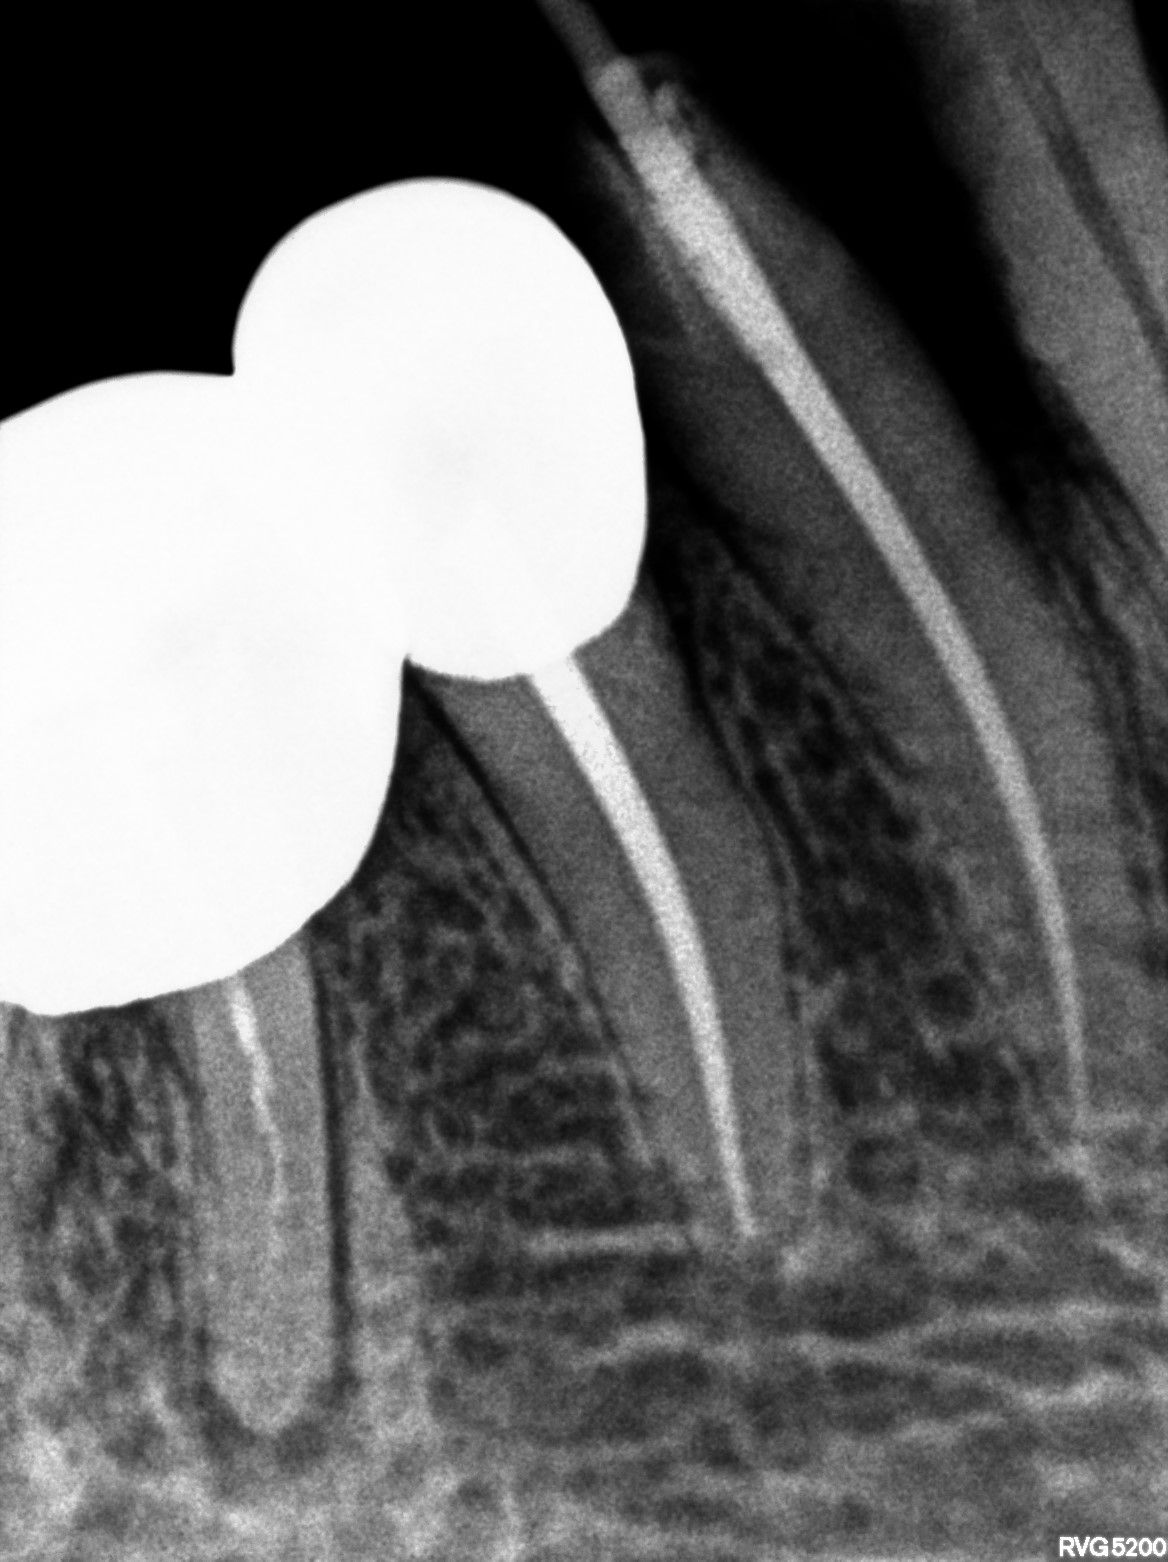

Dental Radiographs FHIR: DocumentReference · LOINC 24641-7

xray_1772525715_0.jpg

24641-7